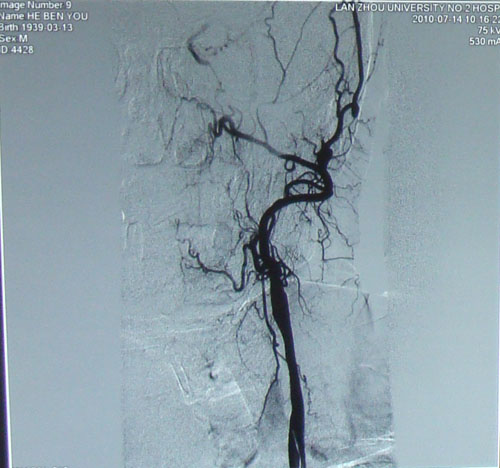

颈动脉DSA示:右侧颈动脉狭窄。

颈动脉超声:双侧颈动脉内膜增厚并斑块形成;左侧颈内动脉闭塞;右侧颈内动脉狭窄(70%-99%);左侧颈总动脉狭窄(50%-69%);右侧颈外动脉狭窄(<50%)

左侧颈内动脉中度狭窄

右侧颈内动脉可看到细微现状血流